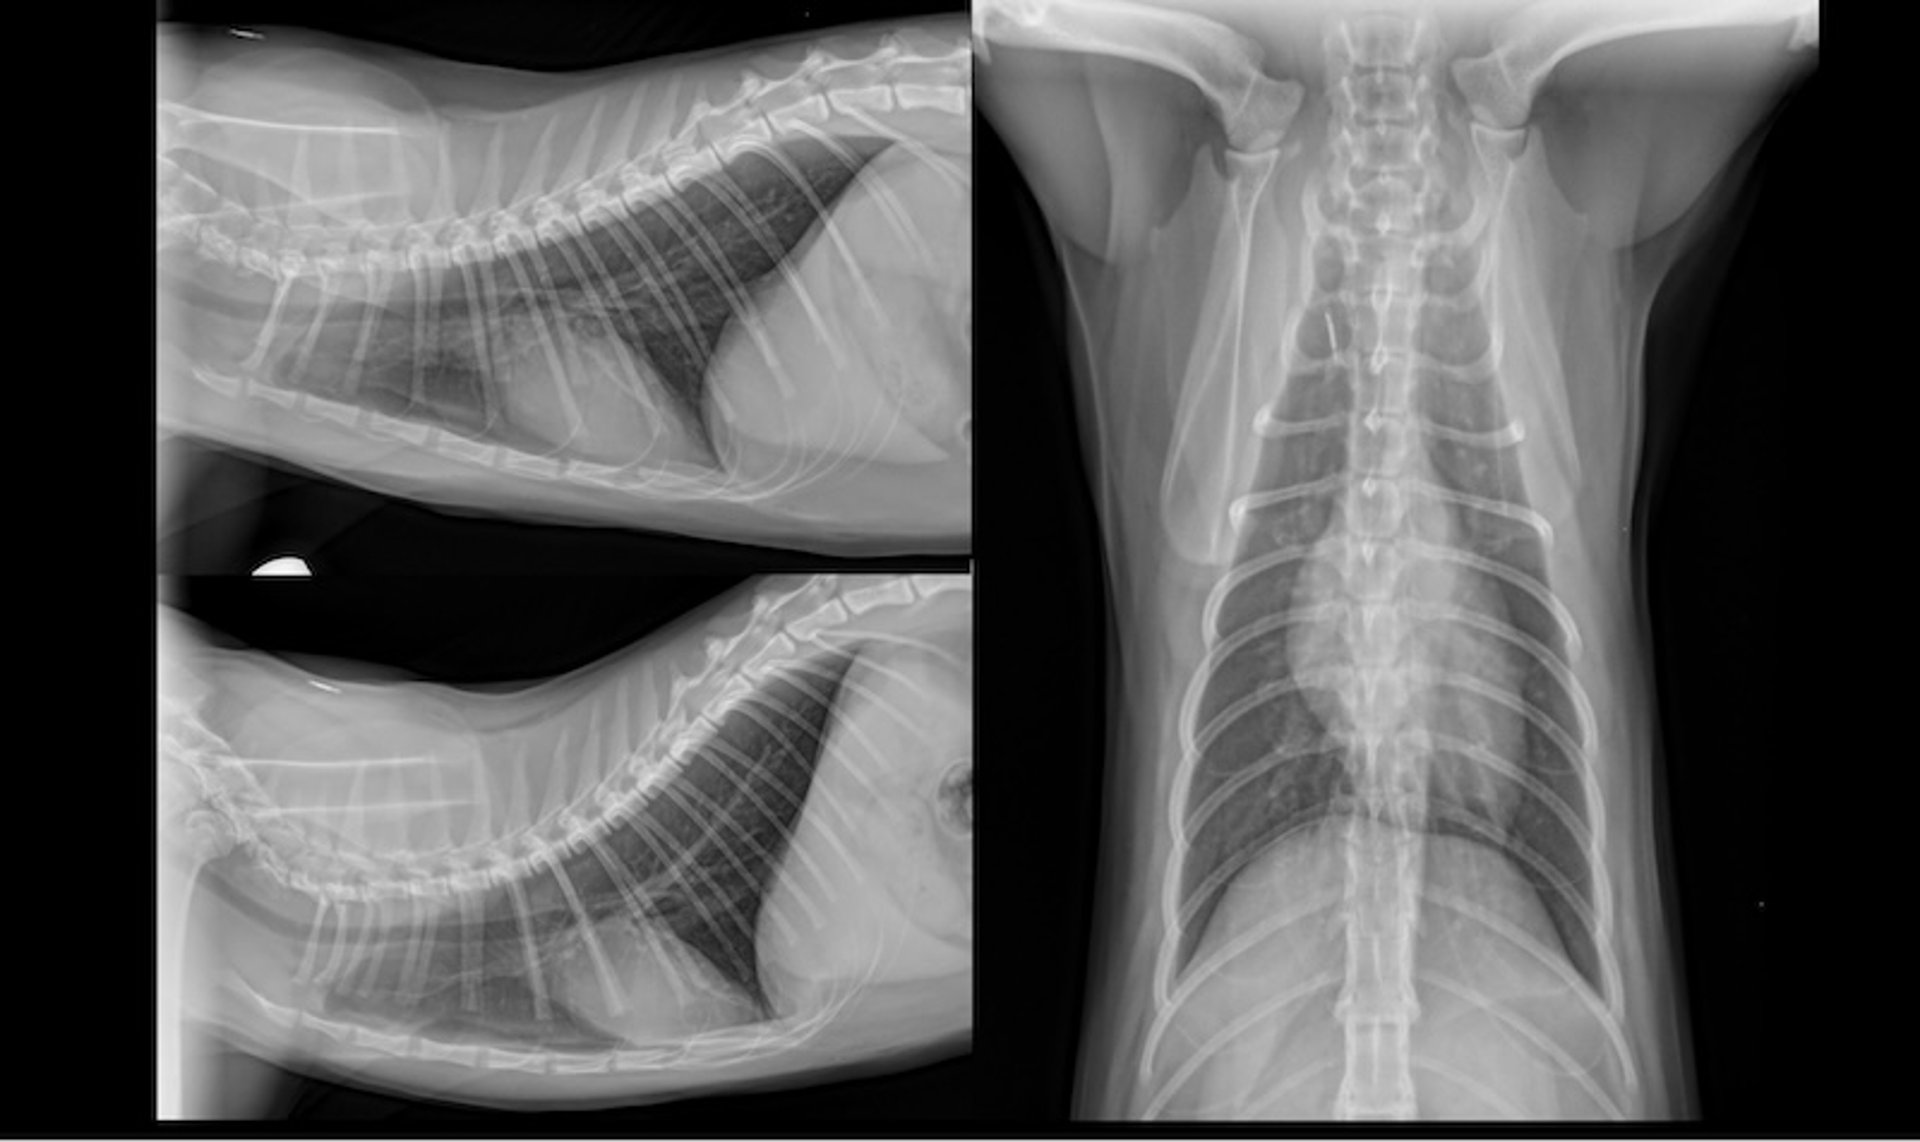

Radiografías de tórax en 3 vistas bien posicionadas en un paciente felino: lateral derecha (arriba a la izquierda), lateral izquierda (abajo a la izquierda) y ventrodorsal (derecha).

Cortesía del Dr. Timothy Manzi.